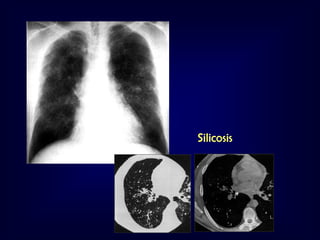

Silicosis

Inhalation of high concentrations of silicon dioxide

•

Fine interstitial opacities with B Kerley’s lines (early)

Multiple nodular shadows scattered in the lungs (classic)

• Sparing apex and base

• Calcification may occur

Progressive massive fibrosis



Nodules enlarge and coalesce to form masses

Bilateral, almost symmetrical

• Almost always in the upper ½ of the lungs

• The more the fibrosis, the less apparent

nodules